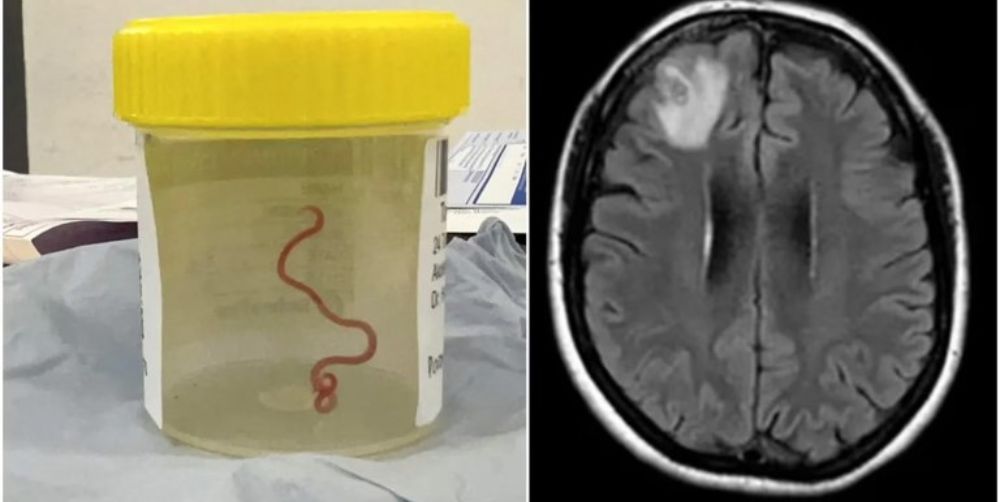

Una mujer australiana de 64 años padecía síntomas extraños desde hace mucho tiempo y los científicos descubrieron que se trata de un gusano parásito de 8 cm de longitud. Es el primer caso registrado en un ser humano.

La ciencia lo identificó como un gusano redondo que se suele observar en la pitón de alfombra o pitón diamantina. La mujer, oriunda de Canberra, se había sometido a una intervención quirúrgica, luego de presentar dolor abdominal, falta de memoria y depresión.

La especie del parásito es conocida como ophidascaris robertsi, según el artículo de la revista.